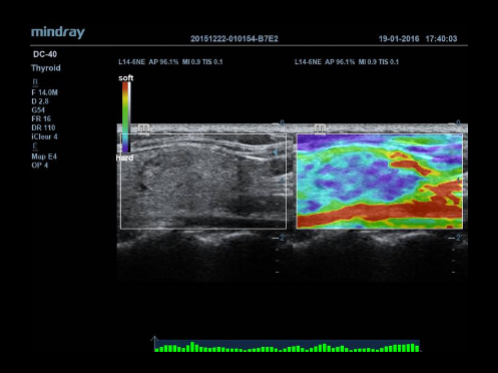

Tissue Doppler Imaging with Quantitative Analysis (TDI and TDI-QA)

Supported by MindrayŌĆÖs unique 3T technology with single crystal, the M7 premium significantly improves the performance of Tissue Doppler Imaging. With the added quantitative analysis package with comprehensive parameter outputs such as velocity, strain and strain rate, the TDI-QA performs with ease at the bedside.